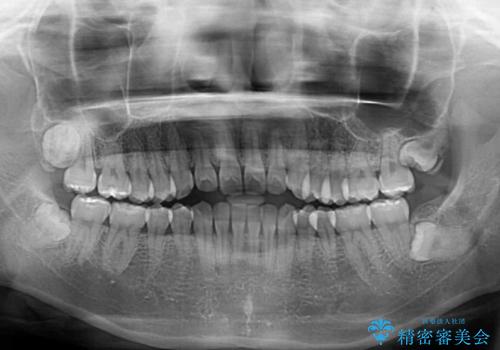

- 前歯の上下スペースによる話しにくさを気にして来院された患者様です。

インビザラインにより上下の前歯の隙間を閉じていくこととしました。

上下の奥歯を圧下させるようにすることで、前歯を接触させるように計画しました。

隙間に舌が入り込むことが話しにくさに繋がっていたため、舌の筋肉のトレーニングも並行して行い、話しにくさの改善と後戻りの抑制を図りました。